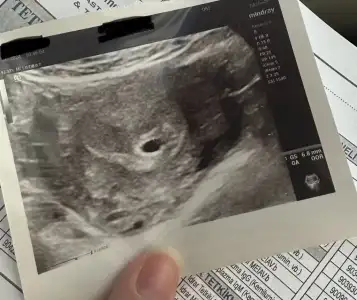

Kızlar bugün ilk kez kontrole gittim . Kese bu şekil göründü normal mi . 5+2 son adet tarihine göre . Yorumlayabilir misiniz. 2 hafta sonraya randevu verdi kalp atışı için

Teşekkür ederim sizede hayırlı olsun Pek açıklayıcı değildi. Kalp atışı duymadan kimseye söylemeyin dedi